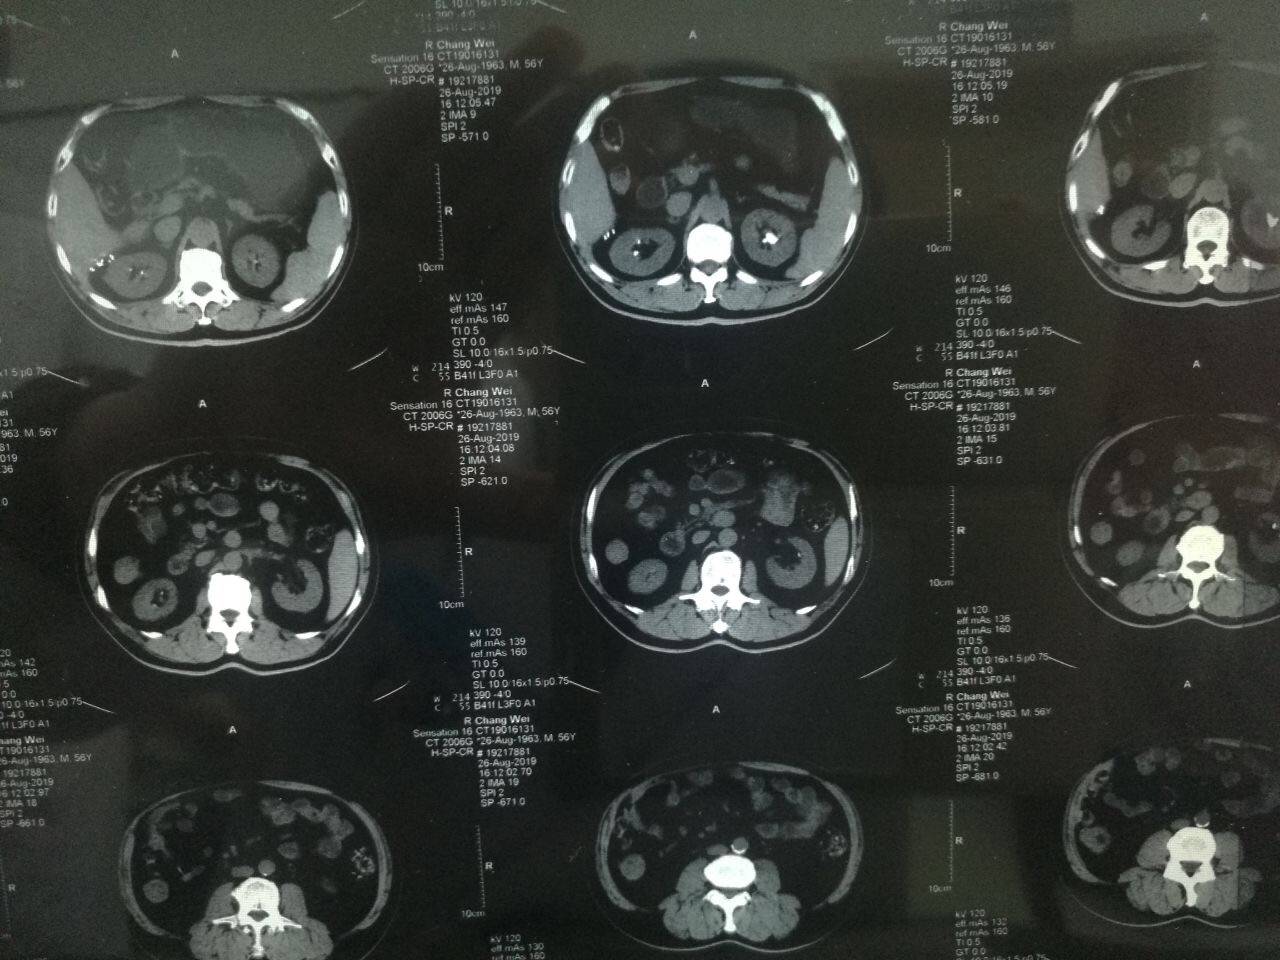

?2019年8月22日,家住陕西永寿县的一岁半幼儿笑笑(化名)突然出现阵发性哭闹,且伴有腹痛、小便不畅、尿色深黄浑浊等症状,奶奶遂带其前往永寿县医院诊治,县医院诊断为“包皮炎”,并给予局部涂擦碘伏。可没想到5天后,笑笑再次哭闹不止,且完全不能自解小便,尿液自尿道溢出,下腹胀满。再次来到县医院治疗,经过CT及超声检查显示,孩子尿潴留,尿道结石,肾结石。由于患儿年纪小,病情更为复杂和紧急,经推荐笑笑从县医院转入21点游戏攻略站 泌尿外科进行治疗。转入21点游戏攻略站 时,患儿腹胀如鼓,时不时有尿液自尿道滴出,哭闹异常剧烈。见此情景,泌尿外科张争春医生立即带领王卫妮护士长给患儿进行导尿,但因结石恰好卡在尿道,导尿管难以插入,张争春医生在患儿的哭闹声中,经过多次努力,终于将导尿管成功插入,暂时缓解了患儿的危急症状,也为后续的治疗创造了机会。